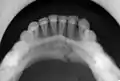

Panoramic radiograph of a simple mandible fracture of the right mandibular body, minimally displaced. Note that the teeth to the left of the fracture do not touch

Panoramic radiographs are tomograms where the mandible is in the focal trough and show a flat image of the mandible. Because the curve of the mandible appears in a 2-dimensional image, fractures are easier to spot leading to an accuracy similar to CT except in the condyle region. In addition, broken, missing or malaligned teeth can often be appreciated on a panoramic image which is frequently lost in plain films. Medial/lateral displacement of the fracture segments and especially the condyle are difficult to gauge so the view is sometimes augmented with plain film radiography or computed tomography for more complex mandible fractures.